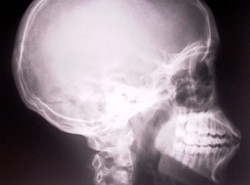

Wyobraź sobie, że miałeś wypadek. Straciłeś część kości udowej. Żeby ją uratować, lekarze zamiast wszczepić Ci kawałek syntetyku, wstrzykują komórki macierzyste. A te odbudowują tkankę kostną. Tak w przyszłości będą leczone niektóre urazy - przewiduje DZIENNIK.

Komórki macierzyste to wielka nadzieja współczesnej medycyny regeneracyjnej. Mogą się bowiem bez przeszkód przekształcać w budulec dla dowolnej tkanki naszego ciała. Wydawać by się zatem mogło, że za ich pomocą możemy odtworzyć kości zniszczone podczas wypadku czy choroby. Zwłaszcza że wyniki doświadczeń przeprowadzanych na komórkach zwierzęcych in vitro (czyli hodowanych w probówce) oraz in vivo (eksperymentów na żywych organizmach, np. gryzoniach) były bardzo obiecujące. Jednak eksperymenty na ludziach nie dawały równie zadowalających rezultatów.

Holenderom udało się znaleźć rozwiązanie tego problemu. Jak tłumaczy dr Ramakrishnaiah Sidappa z Instytutu Technologii Biomedycznych Uniwersytetu Twente w Holandii, sposobem na to, by naprawić duże ubytki kości, jest wszczepienie w uszkodzone miejsce tzw. mezenchymalnych komórek macierzystych (tzw. MSC) pobieranych ze szpiku kostnego. Komórki takie można pobierać wprost od osoby, która chce się leczyć tą metodą. Dzięki temu pokonuje się pierwszą przeszkodę związaną z wszelkimi transplantacjami, a mianowicie problem zgodności tkankowej. Ponieważ przeszczepia się własne komórki organizmu, nie powinny zostać one odrzucone.

Dlatego uczeni zaczęli szukać czynnika, który zadziała na owe komórki jak swoisty przyspieszacz wzrostu. W tym celu wyizolowali komórki MSC ze szpiku kostnego pobranego od 14 pacjentów w wieku 31 - 82 lat, przechodzących poważne zabiegi ortopedyczne. Następnie uzyskane w ten sposób komórki poddano działaniu specyfików uaktywniających wydzielanie pewnego enzymu, tzw. kinazy białkowej A PKA. Okazało się, że taki zabieg przyniósł świetne rezultaty. W doświadczeniach in vitro spowodował zwiększone wydzielanie się czynnika wzrostu kości i nawet 5-krotnie przyspieszał osteogenezę, czyli formowanie się tkanki kostnej.